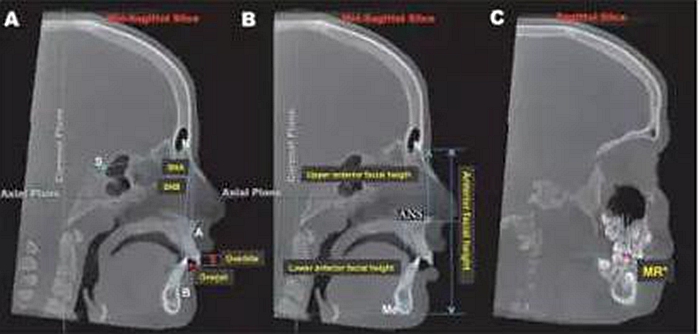

图1:3D参考平面的的定为:轴面:通过左右眶下点及右侧耳点的平面;冠状面,通过左右耳点并垂直于轴面的平面;矢状面,通过鼻根点并垂直于轴面及冠状面的平面。

图2:矢状面上标志点的测量:A,SNA, SNB, 覆合覆盖的测量;B,上前面高N-ANS,下前面高ANS-Me的测量;C,左右磨牙关系的测量:上颌第一磨牙近中颊尖与下颌第一磨牙近中颊沟的水平距离,但在扩弓完成的即刻(T2)因为磨牙带环的阻挡,该数据无法测量。